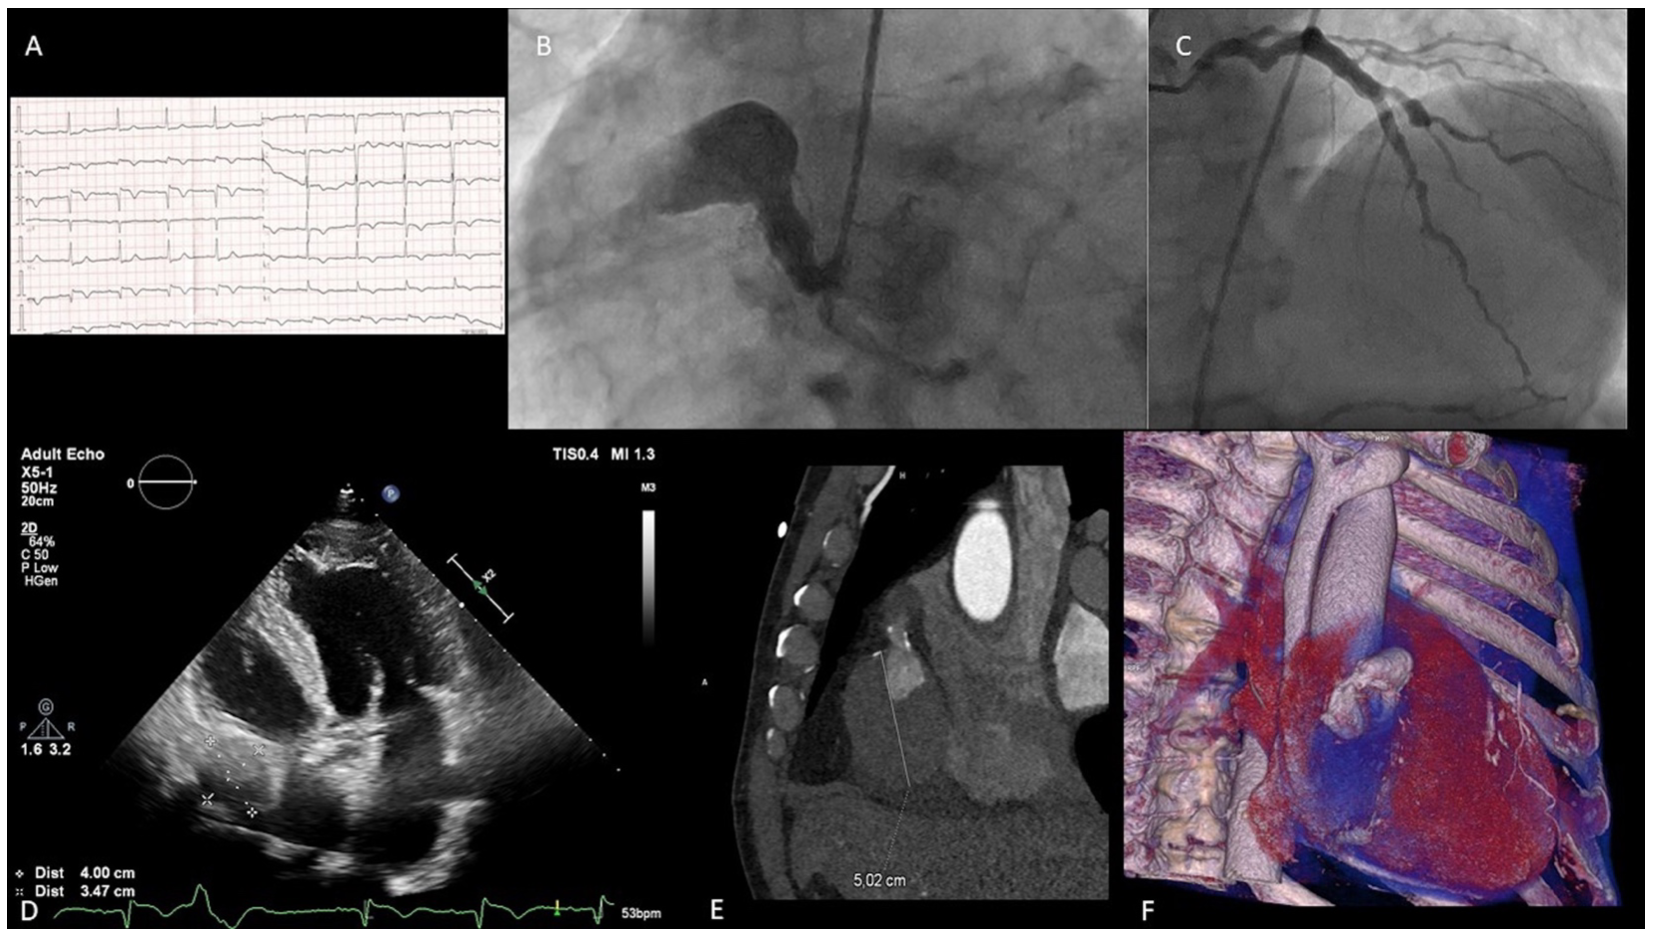

A 74-year-old man with diabetes mellitus reporting chest pain for the duration of one week and with declining troponin levels was admitted after an episode of syncope. Q wave and ST elevations with T inversions were seen on the echocardiogram (ECG) in inferior wall leads (Figure 1A). Bedside aortic dissection was excluded, ejection fraction was 15%. In the cath lab, a giant right coronary aneurysm was visualized with artery occlusion medially and possibly two cavities. RCA and circumflex artery (CX) had common origin (Figure 1B) (Video 1). The left anterior descending artery (LAD) gave collateral flow to the RCA (Figure 1C) (Video 2). The heart team was consulted and decided on subsequent imaging. The next ECG in modified projections showed echo negative cavity with dimensions measuring 4 cm x 3.47 cm (Figure 1D) (Video 3). In computed tomography, prospective ECG-gated acquisition after intravenous administration of 70 ml of the contrast agent Ultravist 370 (Bayer) showed partially thrombosed first aneurysm in second segment of RCA (4 cm x 3 cm), and an almost completely thrombosed second aneurysm in the third segment of the RCA (5.02 cm x 5 cm). Sagittal view of both aneurysms is shown in (Figure 1E) with dimensions of the thrombosed aneurysm exceeding 5 cm. Next, 3D volume rendering reconstruction was done (Figure 1F). After recovery of ejection fraction, the patient was treated conservatively with an option for surgical repair on the aneurysms.